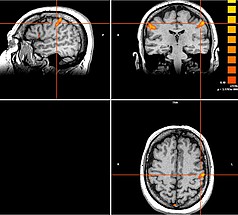

Bei bestimmten Bewegungsstörungen, die nicht oder nicht mehr ausreichend auf eine medikamentöse Therapie ansprechen, ist es möglich, die hierfür verantwortlichen Hirnareale durch die sog. Tiefe Hirnstimulation zu beeinflussen. Hierbei werden feine Elektroden in das Gehirn eingesetzt, um fehlerhafte Nervenstrukturen mit elektrischen Impulsen zu aktivieren oder zu hemmen. Beim Morbus Parkinson, dem essentiellen Tremor oder der Dystonie sind beispielsweise spezifische Hirnareale überaktiv, die dann gezielt durch die Tiefe Hirnstimulation gehemmt und die Symptome wie Zittern oder Muskelsteifigkeit dadurch unterdrückt werden können. Die Hirnregionen selbst bleiben dabei intakt, sodass die Stimulation jederzeit rückgängig gemacht werden kann. Die elektrische Stimulation wird durch einen Impulsgeber gesteuert, der ähnlich wie ein Herzschrittmacher unter die Haut an der Brust der Patient:innen implantiert wird. Die Einstellungen des Impulsgebers lassen sich von außen jederzeit verstellen, sodass die Stimulation an veränderte Bedürfnisse der Patient:innen stets angepasst werden kann.

Neben den Bewegungsstörungen sind mittlerweile auch einige neuropsychiatrische Erkrankungen, wie die Depression oder Zwangsstörungen bekannt, bei denen fehlerhafte Hirnareale durch die Tiefe Hirnstimulation verändert (=moduliert) werden können. Bei schweren therapieresistenten Verläufen kann auch hier dieses Verfahren angeboten werden.

Tiefe Hirnstimulation bei psychiatrischen Erkrankungen

Neben den Bewegungsstörungen sind mittlerweile auch einige neuropsychiatrische Erkrankungen, wie die Depression oder Zwangsstörungen bekannt, bei denen fehlerhafte Hirnareale durch die Tiefe Hirnstimulation verändert (=moduliert) werden können. Gemeinsam mit dem ZI Mannheim erforschen wir neue Zielstrukturen und Indikationen.